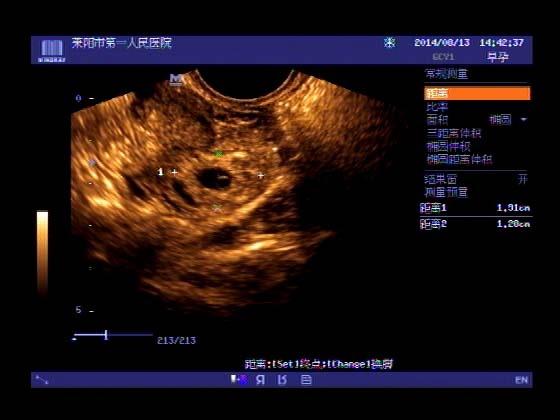

超声入门贴341:宫外孕(阴超的魅力)

女,32岁,停经15天,

一周前在上极医院检查:化验尿HCG阳性,血HCG400多,超声检查问见明显孕囊,让随访。

看见卵黄囊啦~孕囊型的吧?

还能看到卵黄囊,真不错